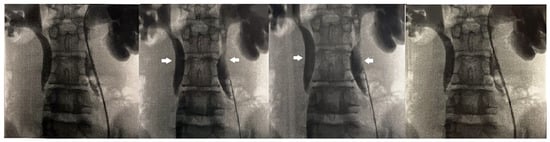

The anterior urethra presented an adequate caliber at urethrocystoscopy using a pediatric 9.5 F scope (KARL STORZ SE & Co., KG, Tuttlingen, Germany). Hypoplastic veru montanum and a blind punctiform orifice, representing the remnant of the resected duplicated urethra, were observed distally to the hypertrophic posterior rim of the bladder neck. The bladder appeared large with slightly trabeculated wall. The right ureteral ostium was narrow and located at the apex of the mound of previous bulking agent implantation, whereas the left ureteral ostium appeared narrow and displaced laterally. After catheterization of both ureteral orifices, retrograde pyelography showed dilatation of both ureters and all calices, which became progressively narrow from the iliac tract to their entry into the bladder, especially on the left side, with delayed contrast washout (Figure 1). Two indwelling 4F ureteral catheters were placed into the left ureter for 8 days to dilate the ureteral orifice. The patient was prescribed urotherapy (alpha-blockers), bladder training with double voiding, and clean intermittent catheterization (CIC) twice a day. No significant improvement was observed at 3-month control, and the patient was poorly compliant with CIC. In the following 8 months, he presented three further episodes of orchiepididymitis, treated with medical therapy. US confirmed persistent bilateral severe hydronephrosis and megaureter, very high bladder capacity (max volume 800 mL), and abnormal PVR (460 mL). To rule out the diagnosis of neurogenic bladder, lumbosacral magnetic resonance imaging (MRI) excluded any intrinsic anomalies of the spinal cord. Urodynamic study revealed a maximum cystometric capacity of 1002 mL, a maximum detrusor pressure of 8.4 cm H2O, and a PVR of 350 mL, consistent with hypotonic and hyporeflexic bladder (Figure 2).

Figure 1. Retrograde pyelography showing bilateral calyceal and ureteral dilatation (white arrows) and delayed contrast washout.